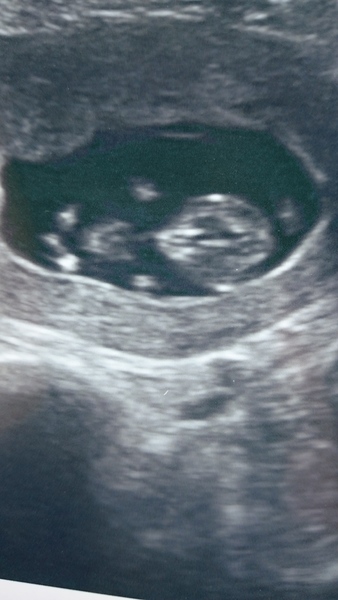

Hello everyone. I'm new. Been around for a while, lurking. I'm 10+6 today, edd 3rd Oct. I've had my second private scan this afternoon, just for reassurance as there was some confusion over my dates. Here's my little one Grin can finally breathe! (sorry it's the wrong way, can't seem to rotate it!)

October baby bus take 3- booking in appointments and scans, here we come!

Never mind, obviously did it automatically.